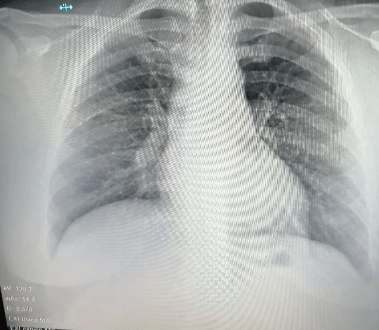

Bronconeumonía

Es la inflamación de los bronquiolos finos y sacos alveolares de los pulmones, producida generalmente por virus y bacterias. Los bronquiolos son los pequeños conductos que hay dentro de los pulmones.

Neumonía

Es una infección del pulmón que puede ser causada por múltiples microorganismos (bacterias, virus y hongos). Las neumonías se clasifican según se adquieren en el día a día de una persona (neumonía adquirida en la comunidad) o en un centro sanitario (neumonía hospitalaria).

Las infecciones de los pulmones, denominadas neumonías, son más graves, pero menos comunes

A causa de estos padecimientos, algunos pacientes necesitan rehabilitación pulmonar y broncodilatadores, medicina que ayuda a mantener abiertas las vías respiratorias en el pulmón, haciendo más fácil la entrada y salida de aire